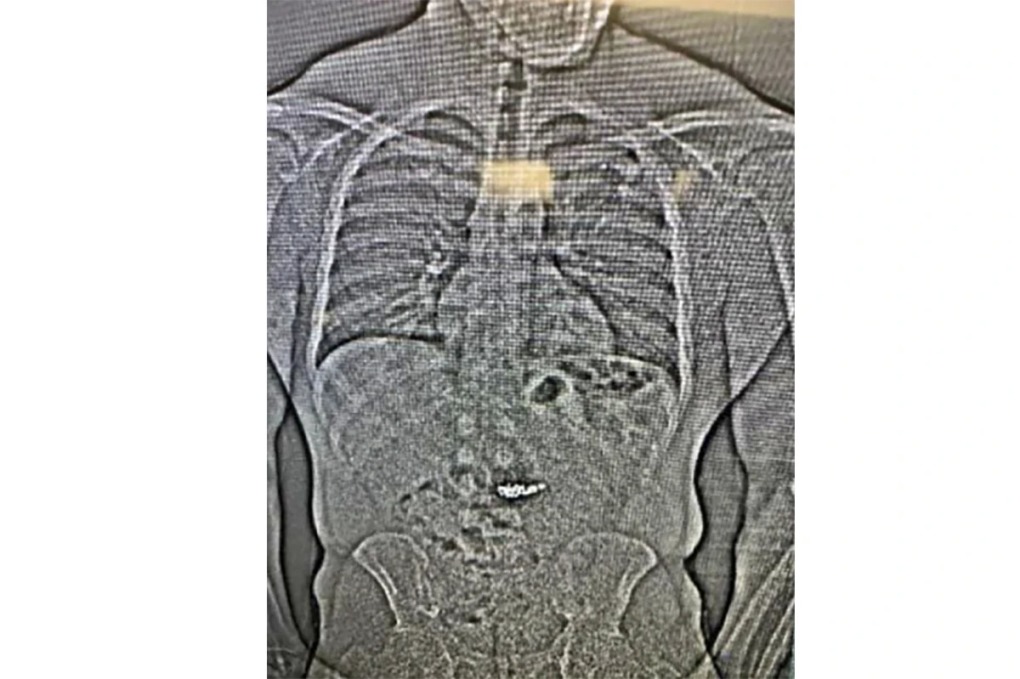

Phim X-quang cho thấy vật thể lạ trong hệ tiêu hóa của Gilder. Ảnh: AP

Ảnh chụp X-quang cho thấy có vật thể lạ trong đường tiêu hóa của Gilder và giới chức nghi ngờ đây là các bông tai kim cương trị giá 770.000 USD bị cướp, nhưng cần chờ cảnh sát hạt Washington xác nhận bằng cách thu thập sau khi Gilder thải ra qua đường tiêu hóa.